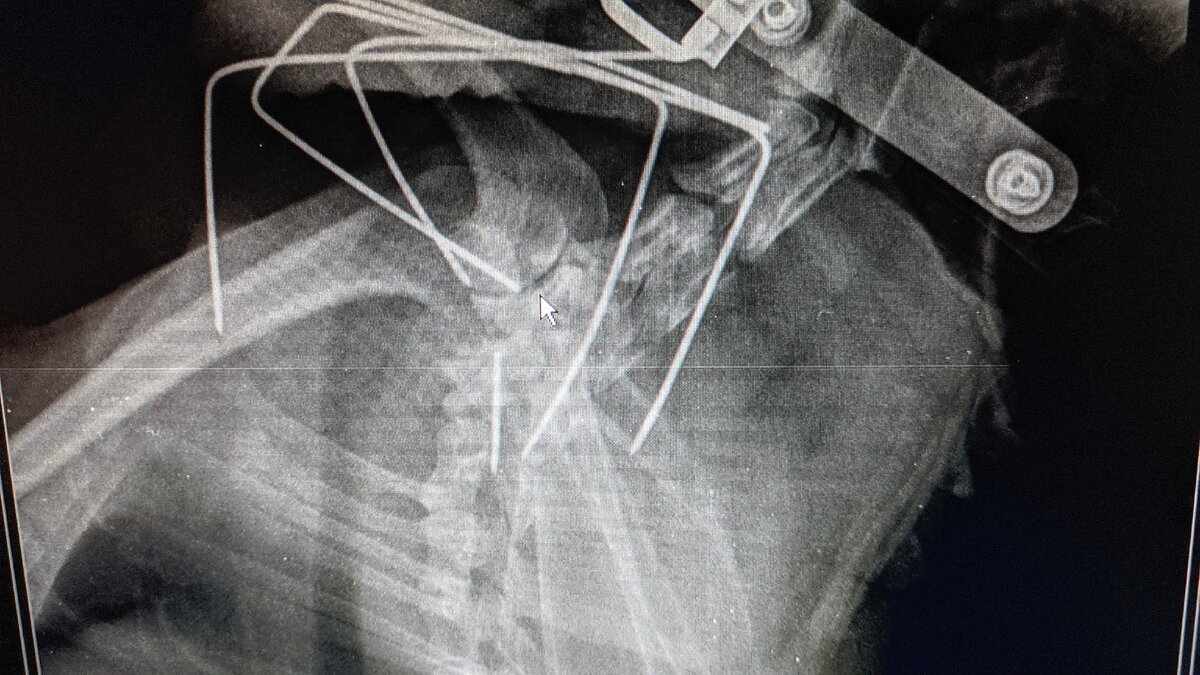

Приехали мы на операцию, её оформили, забрали на стационар, там её покормили (нам сказали самим не кормить перед операцией, только вода) и сказали ждать. Мы приехали к 12 00 забрал я её только 18 30 , операция была тяжелая, но всё сделали как нужно

Как видите разница в методах колоссальная)

Приехали на последнюю операцию. Она уже там всех узнала, даже кота который там живёт) и не нервничала как обычно в незнакомых местах. Во время операции ей убрали скрепку которую поставили на предыдущей операции и кусок стальной спицы (доставали её, как сказали, через лопатку) . Всё прошло хорошо, но с технической стороны было сложно, но врач справился. Спасибо ему за проделанную работу.